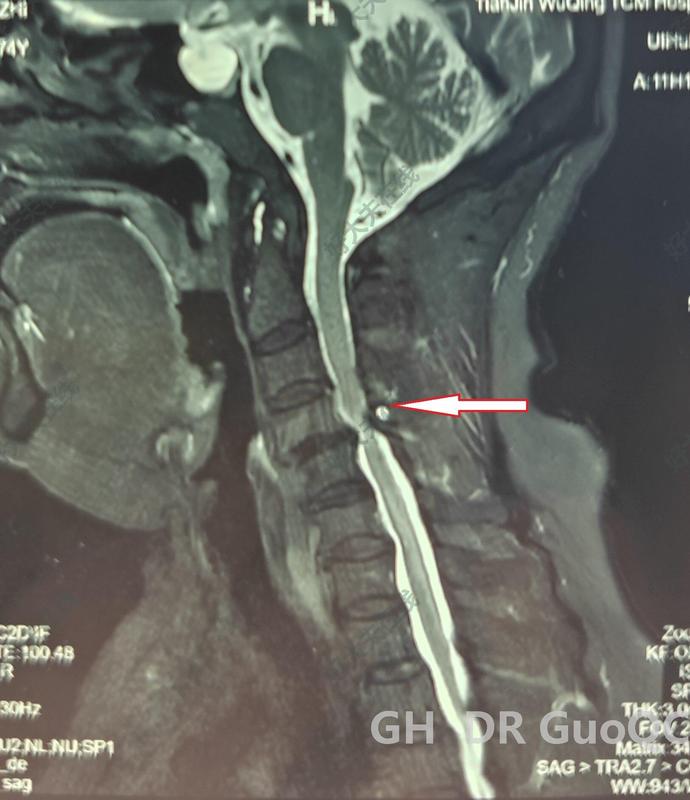

不少患者查出頸椎病后,發(fā)現(xiàn)不是頸椎受壓就是脊髓受壓,這兩種情況有什么不同呢?哪一種更嚴(yán)重呢?如果既壓迫到神經(jīng),又壓迫到脊髓,又該怎么辦呢?頸椎病壓到神經(jīng)和脊髓,有什么不同?事實上,這個問題是在對比神經(jīng)根型頸椎病和脊髓型頸椎病。頸椎病由于頸椎退化等各種原因?qū)е轮車纳窠?jīng)根、脊髓、血管等組織受壓,導(dǎo)致出現(xiàn)一系列癥狀。根據(jù)受壓組織不同,頸椎病又分為許多類型,其中最常見的就是神經(jīng)根型頸椎病,最嚴(yán)重的就是脊髓型頸椎病。顧名思義,神經(jīng)根型頸椎病常由于頸椎間盤突出等原因?qū)е律窠?jīng)根受壓,患者常會出現(xiàn)上肢的放射性疼痛、麻木、無力等癥狀;而脊髓型頸椎病壓迫到脊髓,患者除了上肢癥狀外,還會出現(xiàn)下肢的走路踩棉花感、走路不穩(wěn)等情況。這兩種類型的頸椎病治療方案也略有不同,神經(jīng)根型頸椎病多數(shù)情況下保守治療就可以了,只有患者的病情嚴(yán)重,保守治療無效,嚴(yán)重影響生活了才會考慮手術(shù)干預(yù)。但脊髓型頸椎病是一旦確診就需要盡快手術(shù)的,保守治療效果不好,而且脊髓長時間受壓,可能會導(dǎo)致一些不可逆的功能障礙。既壓到神經(jīng),又壓到脊髓,這種頸椎病要怎么辦?最近,宣武醫(yī)院王作偉主任接診了一位44歲的女性頸椎病患者。這位患者出現(xiàn)脖子疼痛、僵硬已經(jīng)有3年了,難受的時候會做熱敷、針灸,但在2個月前,她的右側(cè)上肢出現(xiàn)了放射性疼痛,麻木乏力,偶爾時不時還會出現(xiàn)走路腳底有踩棉感,這讓她非常難受,去了當(dāng)?shù)蒯t(yī)院檢查出頸椎病?;颊邽榱诉M(jìn)一步治療,最后找到王主任。從她的片子、查體等檢查結(jié)果上看,她的頸椎生理曲度消失,甚至有點反弓,而且在頸4-7多個節(jié)段出現(xiàn)了椎間盤突出,突出不僅壓迫到了神經(jīng)根,同時也壓迫到了脊髓。這種情況該怎么辦?這樣的情況,王主任建議進(jìn)行手術(shù)治療。兩者都受到壓迫,尤其是她出現(xiàn)脊髓受壓,并出現(xiàn)下肢走路問題,這時保守治療已經(jīng)沒有太大效果,這種情況還是要盡快手術(shù)處理。術(shù)前影像學(xué)資料:在獲得患者和家屬的同意后,王主任為她成功進(jìn)行了手術(shù)治療。手術(shù)對突出的椎間盤進(jìn)行了切除,給神經(jīng)根和脊髓進(jìn)行了徹底減壓,并給頸椎進(jìn)行內(nèi)固定,重建了穩(wěn)定性。術(shù)后,患者的上肢疼痛立馬得到極大緩解,不到第3天,她就已經(jīng)可以戴著頸托獨自行走了,其余的麻木、乏力癥狀也在逐漸好轉(zhuǎn)。術(shù)后影像學(xué)資料:最后,不管您是神經(jīng)根受壓、脊髓受壓,還是兩個都受壓,出現(xiàn)類似上面這些癥狀時,都要及時去醫(yī)院檢查。若單純是神經(jīng)根型頸椎病,對生活影響不大,建議您先保守治療;若是壓到脊髓或兩個都壓到了,就要考慮盡快手術(shù)干預(yù)了。